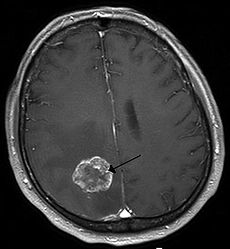

230px-Hirnmetastase_MRT-T1_KM